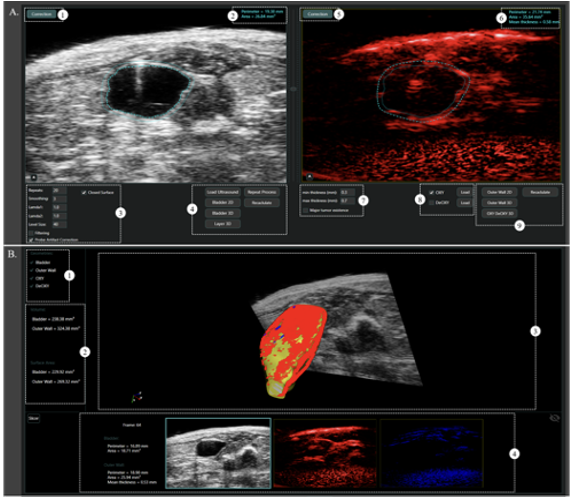

Minimum viable product for automated 3D imaging reconstruction of the bladder and the bladder cancer

Bladder cancer (BCa) is the ninth most common malignancy globally, with an estimated 430.000 new diagnoses annually, while it has the highest lifetime treatment costs per patient of all cancers. Cystoscopy, the gold standard for bladder cancer screening, is an invasive technique that can miss diagnose of small tumours and carcinoma in situ. Therefore, many techniques have been introduced using alternative imaging methods or Artificial Intelligence techniques. Ultrasound (US) is one of the alternative technologies that become widely used among physicians and researchers being non-invasive, faster, safer and cheaper than magnetic resonance imaging and computer tomography. US allows for real-time diagnosis, positioning of medical device and visualization of the efficacy of surgical removal of the lesion, and being non-invasive also for multiple investigations during the follow-up of the patient. In the case of three-dimensional (3D) Ultrasound (US) volume reconstruction and visualization are still time-consuming (in particular for high-volume organ as bladder), being manual or semi-manual processes and requiring well trained people.

In the AIR3D we aim to explore the business potential of the EDIT software in order to bring it closer to the market and to its commercialization by preparing the ground for clinical phase. zThe AIR3D will deliver the go to market roadmap involving manufacturers of imaging devices and researchers, while early adopters will be involved to evaluate the software for its usability, efficiency and effectiveness. The activities that will be performed towards to that objective are analysed in the following sections and are completely differentiate from the activities foreseen in the EDIT work plan that includes development, dissemination and validation activities of novel technological platforms combining ultrasound elastography and photoacoustic imaging on the bladder instilled with targeted plasmonic gold sensors in preclinical models.